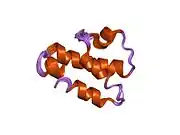

Complement component 5 is the fifth component of complement, which plays an important role in inflammatory and cell killing processes. This protein is composed of alpha and beta polypeptide chains that are linked by a disulfide bridge. An activation peptide, C5a, which is an anaphylatoxin that possesses potent spasmogenic and chemotactic activity, is derived from the alpha polypeptide via cleavage with a C5-convertase. The C5b macromolecular cleavage product can form a complex with the C6 complement component, and this complex is the basis for formation of the membrane attack complex, which includes additional complement components.[5]

- Zuiderweg ER, Nettesheim DG, Mollison KW, Carter GW (1989). "Tertiary structure of human complement component C5a in solution from nuclear magnetic resonance data". Biochemistry. 28 (1): 172–85. doi:10.1021/bi00427a025. PMID 2784981.

- Fredslund F, Laursen NS, Roversi P, et al. (2008). "Structure of and influence of a tick complement inhibitor on human complement component 5". Nat Immunol. 9 (7): 753–60. doi:10.1038/ni.1625. PMID 18536718. S2CID 205361576.